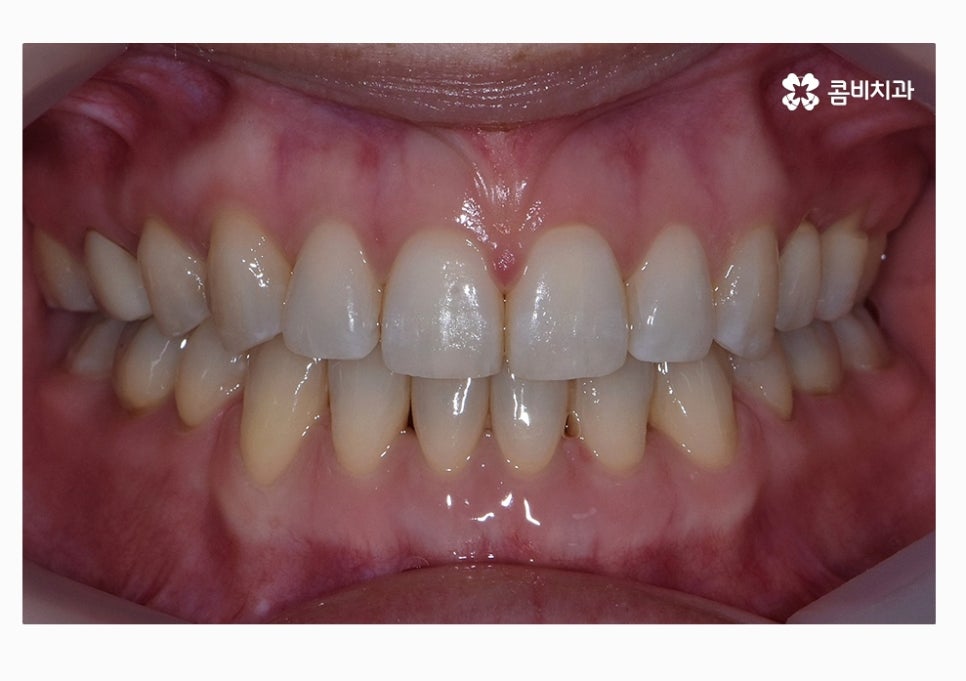

정면으로 치열을 볼 때는 비교적 가지런한 편으로

보이지만 자세히 보면 부정교합에 해당한다는 것을 알 수 있어요.

위 환자분의 경우에는 콤비교정의 치료 경과를 보면

아랫니가 정상교합이 되었고 치열도 보다 가지런하게

변화되고 있음을 알 수 있는데요.

위 케이스는 총 1년 9개월 정도의 치료 기간이 소요되었으며,

개개인마다 치료 결과와 기간은 차이가 있을 수 있습니다.